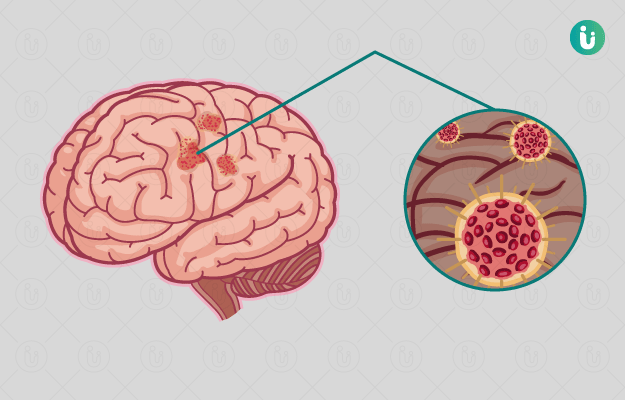

Brain infection causes symptoms prevention and treatment from expert in hindi मस त ष क स क रमण ब र न इ फ क शन क लक षण क रण बच व और इल ज onlymyhealth (फाइल का प्रकार jpg)

Brain Infection Causes Symptoms Prevention And Treatment From Expert In Hindi मस त ष क स क रमण ब र न इ फ क शन क लक षण क रण बच व और इल ज Onlymyhealth